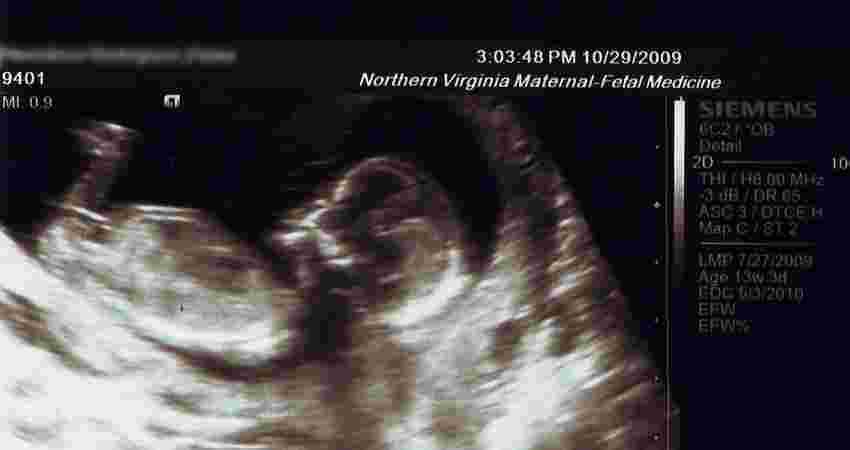

Tadpole or human?

Pro-abortionist: “How do you know what’s growing in the womb is a human life? Do you have a degree in biology?”

TFP member: “I don’t need one. Just like I don’t need to be a weatherman to tell it isn’t raining. What a woman is carrying in her womb is a human being. Common sense.”

Pro-abortionist: “Well, I have a degree in biology, and I can tell you that it’s not a human being until it’s reached 14 weeks.”

TFP member: “Really? Then what were you before 14 weeks?”

Pro-abortionist: “A tadpole.”

TFP member: “You were a tadpole in your mother’s womb? That doesn’t sound very biologically [accurate] to me.”

Pro-abortionist: “I was a tadpole, a chicken, a pig, until a certain week.”

TFP member: “A human embryo will never be anything other than human. From the moment of conception, a distinct human being is formed in the womb.”